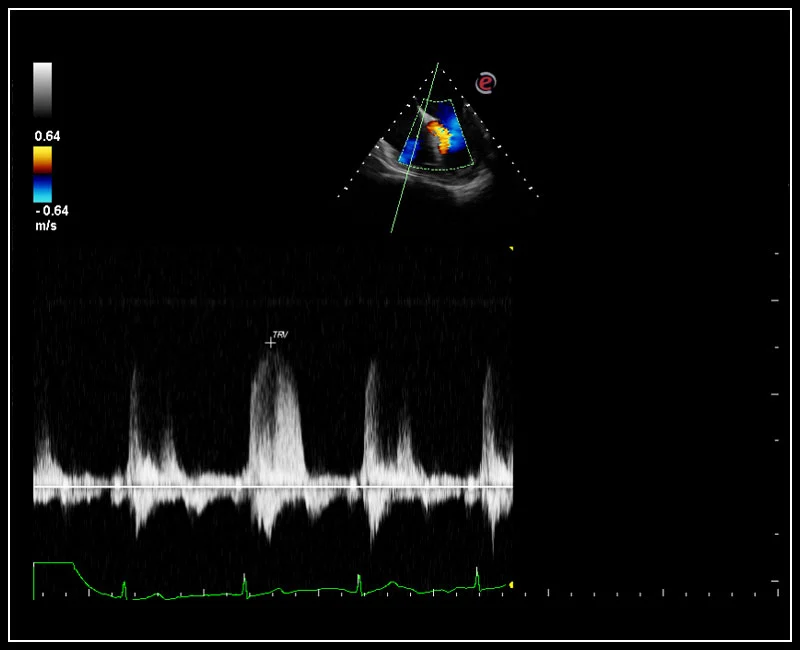

MyLab™Sigma - CW Doppler of Tricuspid regurgitation

MyLab™Sigma - CW Doppler of Tricuspid regurgitation